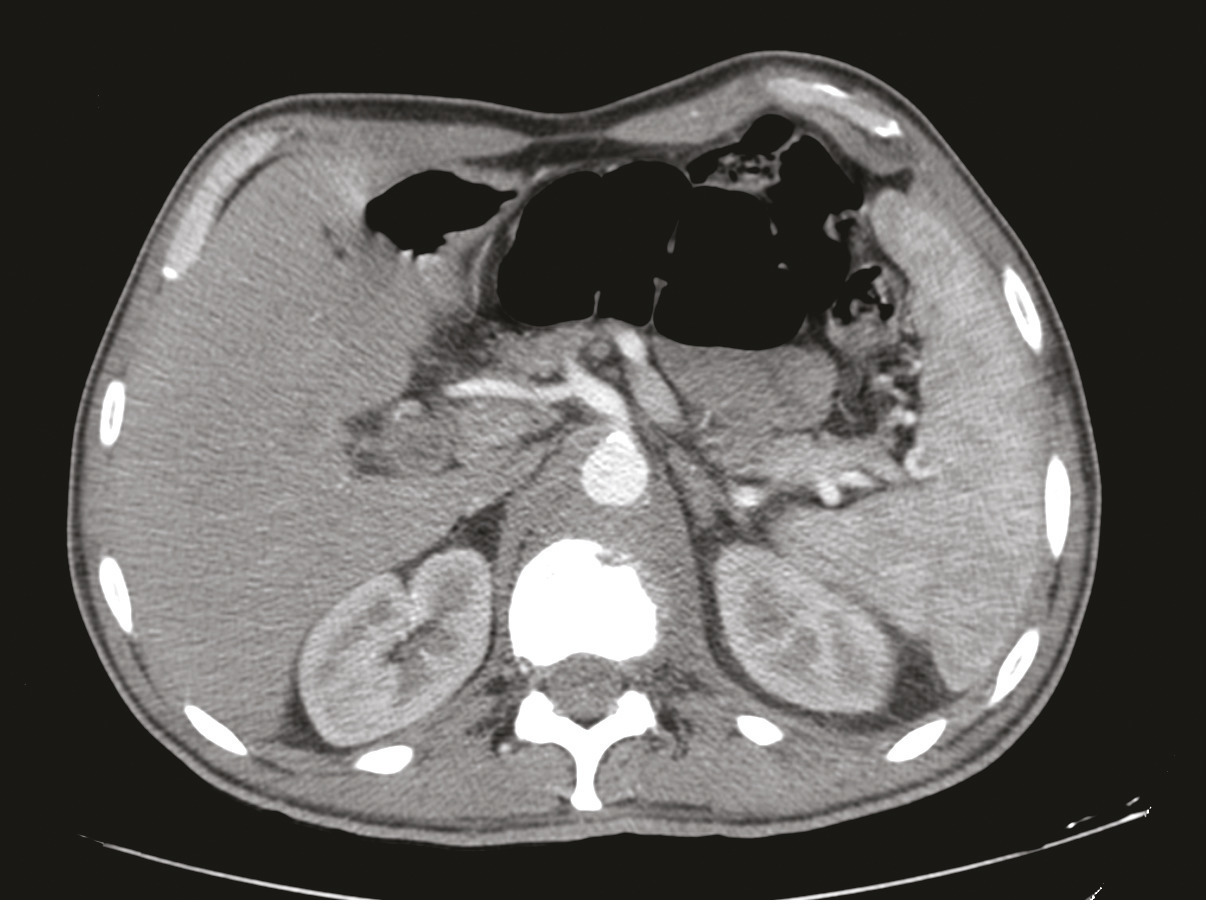

Cet homme de 53 ans consultait pour une douleur de la charnière dorsolombaire à irradiation antérieure, mal calmée par les antalgiques, avec un amaigrissement sans fièvre. L’examen clinique trouvait une raideur rachidienne et le bilan biologique montrait un syndrome inflammatoire. La tomodensitométrie (TDM) abdominale révélait une fibrose rétropéritonéale avec lyse de L1 (fig. 1 ). L’imagerie par résonance magnétique (IRM) montrait un aspect de fibrose rétropéritonéale secondaire, en hyposignal T1 et T2, se rehaussant après injection du gadolinium avec lyse de L1 (fig. 2 ). La tomographie par émission de positons au 18-fluorodésoxyglucose (TEP18-FDG) montrait un hypermétabolisme intense de L1 dont la biopsie scannoguidée révélait un granulome épithélio-giganto-cellulaire cadrant avec une tuberculose (fig. 3 ). Le patient était efficacement traité par les antibacillaires pendant 9 mois.

Figure 1. TDM, coupe axiale, fibrose rétropéritonéale refoulant l’aorte en avant avec lyse de L1.